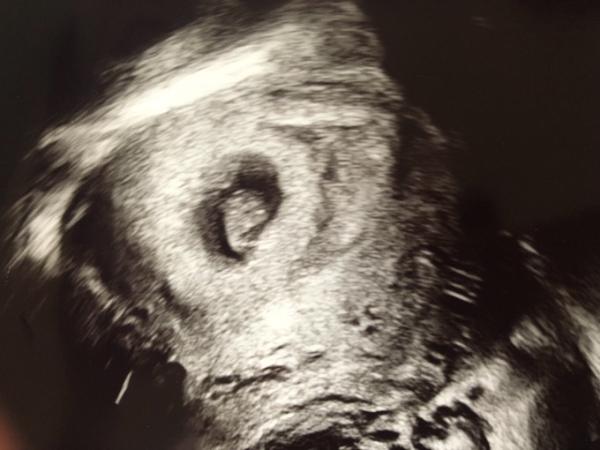

Ich bin erleichtert zurück von unserem ersten Ultraschalltermin. Es ist alles so wie es sein soll. Bei 7+0 und einer SSL von 0,98 cm durften wir einen Herzschlag hören. Da fiel die Anspannung von mir und die Tränen liefen.

Ein Bildchen haben wir auch noch bekommen. Sieht ganz anders aus als bei unserer Tochter. Und ehrlich gesagt, erkenne ich nicht wirklich was